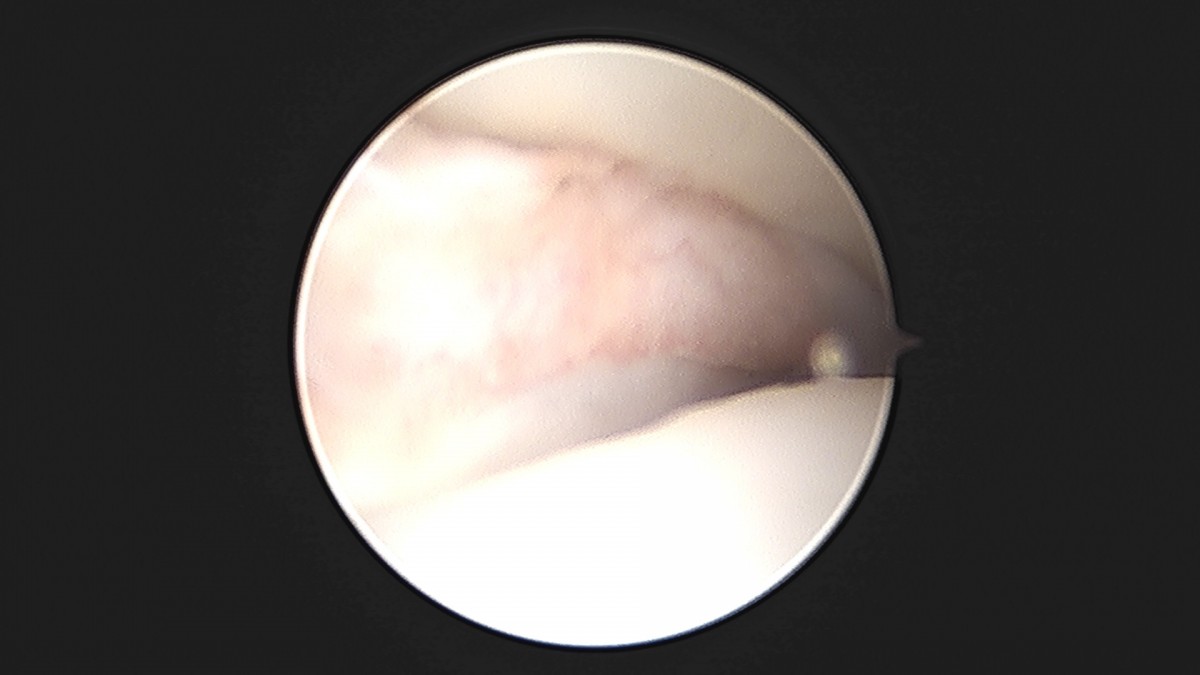

이재상원장님 발목 활액막 절제술 및 인대 봉합술 이승O 환자

작성자 최고관리자 댓글 0건 조회 787회 작성일 25-09-16 15:24